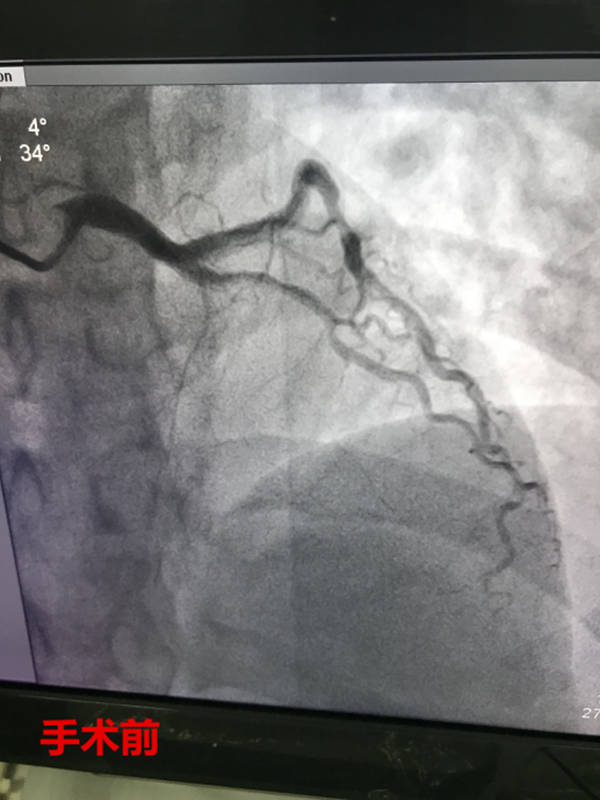

11時12分,路艷主治醫(yī)師護送患者繞行急診科及CCU,直達介入室。徐曉輝主任、耿蓬勃、師軍峰副主任醫(yī)師以及介入室護士郭紀文、于永利、霍貝貝等人員立即就位,手術(shù)開始,穿刺、造影、導(dǎo)絲通過、球囊擴張、支架植入,為患者實施的急診手術(shù)一切都緊張有序的進行……11時45分,手術(shù)順利完成,DtoB時間(患者進入醫(yī)院大門至PCI介入手術(shù)球囊擴張的時間)僅僅26分鐘,遠遠超出了國家對胸痛患者DtoB的時間要求(國家胸痛中心DtoB時間要求<90分鐘)。